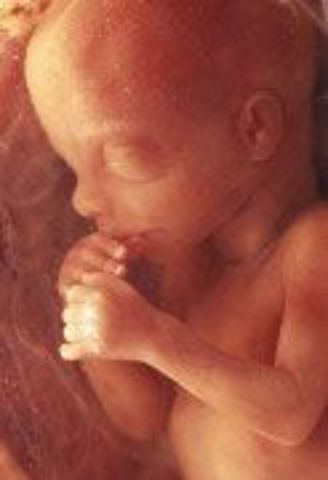

• week 12 Nails

week 12 Nails

the fetus finishes developing its facial profial and finishes developing its vocal chords. the fetus' brain is fuly formed and it feels pain, its pancreas will begin making insulin and the fetus will such on its fingers.

Fact: the fetus will cry silently occasionally in its mothers womb, the fetus has reached 2.5 inches and weighs 0.7 ounces

• week 13 Baby Back Ribs

week 13 Baby Back Ribs

the fetus' ribs will begin development and bones will start replacing the cartilage, the fetus can produce its own insulin to help regulate blood sugar. Measurement of the fetus' movements are possible and you can almost guess the sex of the fetus just by looking at an ultrasound. The fetus has reached 3 inches in size and weights roughly around 1 ounce